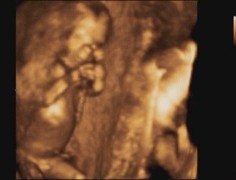

Překvapení v bříšku 🙂